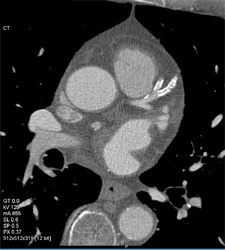

Diagnosis

Diseased LAD